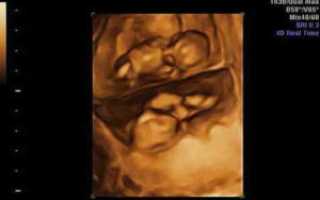

УЗИ на 23 неделе беременности

Акушеры-гинекологи рекомендуют пройти второе УЗИ не позднее 22 недели беременности, но если по каким-то причинам вы опоздали, то пройти ультразвуковое исследование можно сейчас.

На 23 неделе уже можно определить пол ребенка, а также убедиться в том, что его развитие соответствует сроку беременности.

Ультразвуковое исследование на 23 неделе беременности покажет, что происходит с малышом. Данное обследование позволяет выявить отклонения и вовремя назначить лечение. С помощью УЗИ можно сделать фото и определить сердцебиение плода уже со второго месяца.